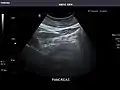

Pancreas

Pancreas: Visualized portions unremarkable.